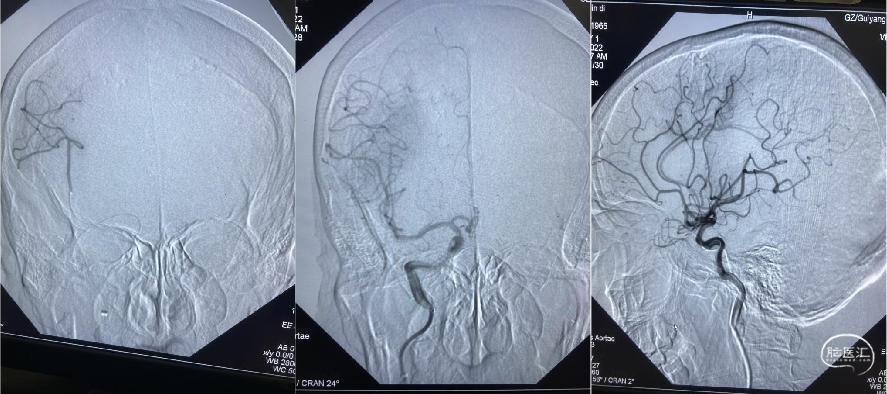

脑血管造影证实:右侧大脑中动脉M1段闭塞。

采用SWIM技术取栓,一把通,远端血流TICI分级3级。

23:25 开始穿刺;

23:35 造影明确右侧大脑中动脉M1段闭塞;

23:55 血管开通成功(距离发病2小时40分钟)。